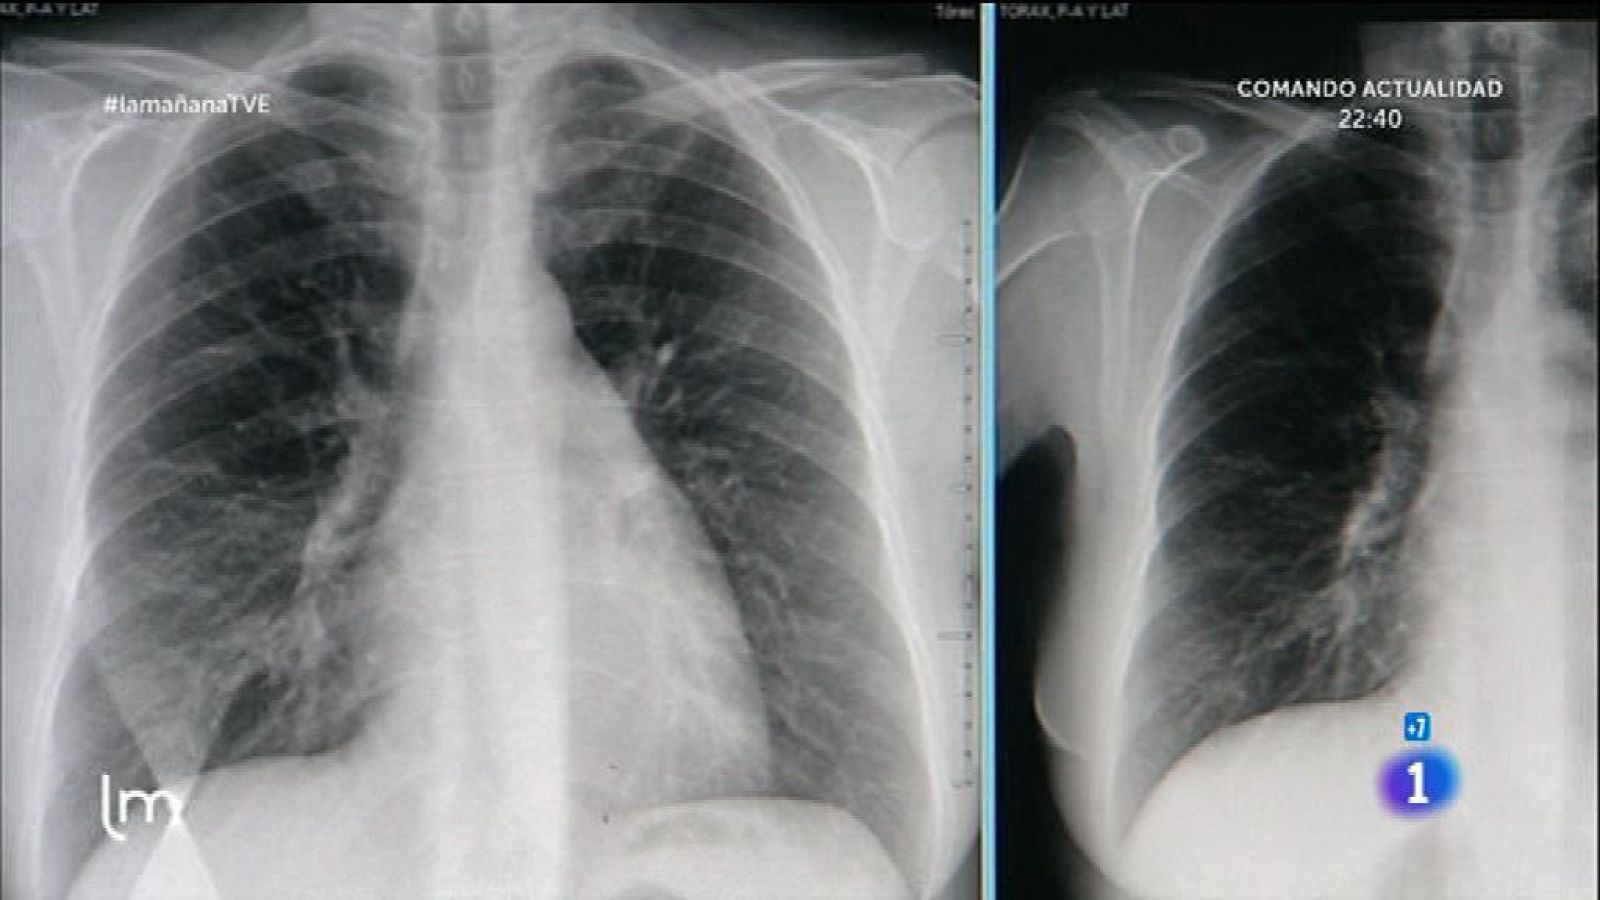

Un 70% de la población tiene problemas respiratorios crónicos y están sin diagnosticar. Pero claro no hay que confundir esos síntomas con los del catarro o la gripe, muy comunes en esta época del año… ¿Por qué tosemos?